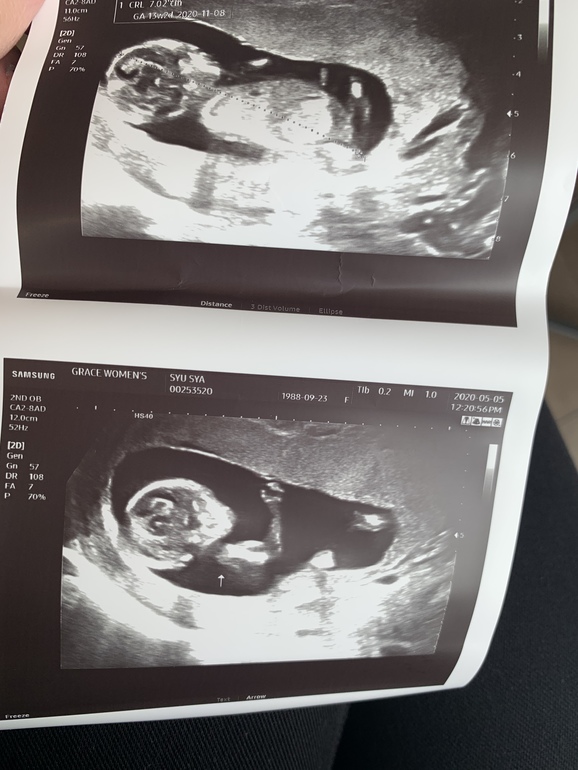

УЗИ, КТГ, доплерВ прошлый раз была у врача ровно в 15 недель. Клинику пока решили не менять, ходим к старому врачу, - он намного опытнее.Тогда всё посмотрели, сказали что норма и отпустили. Наш врач на первом скрининге пол не предполагал, а в 15 недель малыш скрестил ножки, а потом и вовсе отвернулся😌Вчера, поскольку срок 18 и 2 по месячными и 18 и 3 по УЗИ врач сказал сдавать тройной тест. Результаты будут в конце недели, так что остаётся только ждать. По УЗИ всё в норме, но врач говорит, что похоже на девочку. Я даже растерялась как-то, ожидала что подтвердят нам мальчика и начну уже потихоньку что-то выбирать малышу, но наш врач сказал что ничего мальчикового не видит🤷♀️И если раньше мы с мужем больше хотели девочку, то сейчас уже привыкли и полюбили мальчика внутри, над именем думали, а тут...)Придётся ждать ещё 3 недели, видимо. Но это не главное, конечно. Главное, чтобы малыш был здоров🙏Фото УЗИ 15, 18 и 13 недель ( на 13-ой неделе другая клиника)